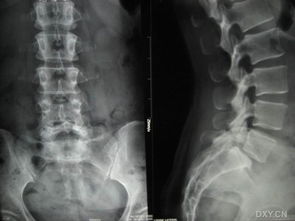

慢性腰痛是腰椎滑脫的主要癥狀。腰椎滑脫是指腰椎椎體間部分或全部錯(cuò)位的一種疾患,一般是上位椎體向前滑移。臨床上分為真性滑脫和假性滑脫。治療前要明確是屬于哪種類型的滑脫。因此除了拍腰椎正側(cè)位片外,還應(yīng)該拍腰椎雙斜位片,必要時(shí)還要行CT和核磁共振檢查以明確是否有神經(jīng)根的壓迫。

當(dāng)發(fā)現(xiàn)腰部不適時(shí),應(yīng)當(dāng)前往醫(yī)院就診,一般的輔助檢查不很昂貴,普通的X線平片或者的腰椎的雙斜位像就可以明確診斷。但是,當(dāng)病情復(fù)雜如合并腰椎間盤突出、腰椎管狹窄或排除腰椎病變時(shí),應(yīng)該進(jìn)一步拍腰椎過伸過屈片以觀察滑脫椎體的穩(wěn)定性,另外還需做CT、核磁共振等檢查以了解神經(jīng)根受壓情況。